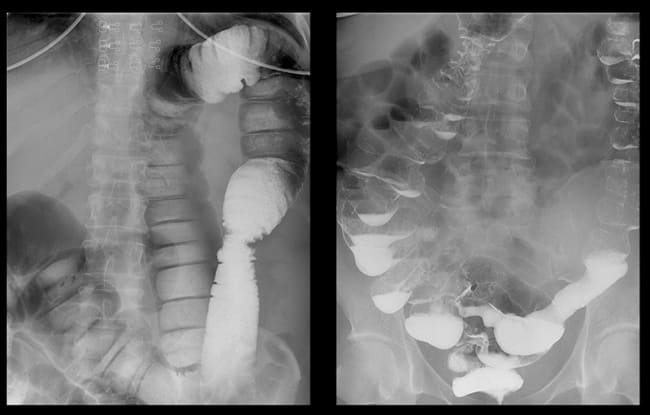

Vastagbélrák egy gyakori székrekedésre panaszkodó nőnél

A vastagbélben lévő székletkövek röntgenvizsgálata